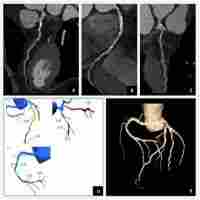

| Abstract | Background Measurement of systolic and diastolic function in animal models is challenging by conventional non-invasive methods. Therefore, we aimed at comparing speckle-tracking echocardiography (STE)-derived parameters to the indices of left ventricular (LV) pressure–volume (PV) analysis to detect cardiac dysfunction in rat models of type-1 (T1DM) and type-2 (T2DM) diabetes mellitus. Methods Rat models of T1DM (induced by 60 mg/kg streptozotocin, n = 8) and T2DM (32-week-old Zucker Diabetic Fatty rats, n = 7) and corresponding control animals (n = 5 and n = 8, respectively) were compared. Echocardiography and LV PV analysis were performed. LV short-axis recordings were used for STE analysis. Global circumferential strain, peak strain rate values in systole (SrS), isovolumic relaxation (SrIVR) and early diastole (SrE) were measured. LV contractility, active relaxation and stiffness were measured by PV analysis. Results In T1DM, contractility and active relaxation were deteriorated to a greater extent compared to T2DM. In contrast, diastolic stiffness was impaired in T2DM. Correspondingly, STE described more severe systolic dysfunction in T1DM. Among diastolic STE parameters, SrIVR was more decreased in T1DM, however, SrE was more reduced in T2DM. In T1DM, SrS correlated with contractility, SrIVR with active relaxation, while in T2DM SrE was related to cardiac stiffness, cardiomyocyte diameter and fibrosis. Conclusions Strain and strain rate parameters can be valuable and feasible measures to describe the dynamic changes in contractility, active relaxation and LV stiffness in animal models of T1DM and T2DM. STE corresponds to PV analysis and also correlates with markers of histological myocardial remodeling. |